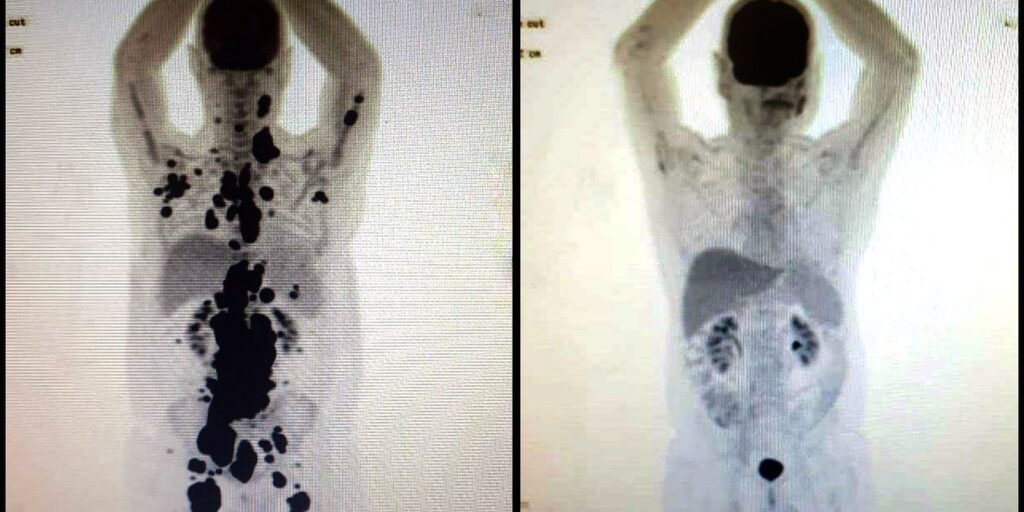

Para um desses pacientes, Paulo Peregrino, a resposta foi imediata, conta o professor de hematologia. “Nesse caso, o que impressiona é a resposta imediata de um paciente que tinha muitos tumores. Então, as imagens [pet scan do corpo do paciente] mostram: tudo que é preto [os tumores] desaparecem completamente em um mês. Repetimos recentemente as imagens, e continua tudo em remissão. Quer dizer, ele está livre do tumor neste momento. Porém, para falar de cura, demora alguns anos, porque, mesmo fazendo isso, a doença pode voltar”, enfatiza.

Diante da notícia da remissão completa do câncer, Peregrino se disse surpreso. “Primeiro, não acreditei que estava daquele jeito, não conhecia aquela imagem [pet scan], não sabia que havia chegado naquele ponto e, ainda, depois que chegou aquele ponto [de remissão], depois do Car T Cell”.